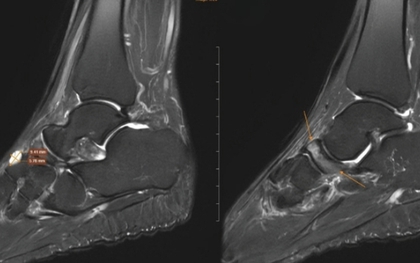

Nữ giáo viên đi khám đau cổ chân, bất ngờ phát hiện bị bệnh 'triệu người có một'

Người phụ nữ đau cổ chân kéo dài sau thời gian chạy bộ liên tục, kiểm tra phát hiện hội chứng hiếm khiến xương bàn chân xẹp, nguy cơ biến dạng vĩnh viễn.